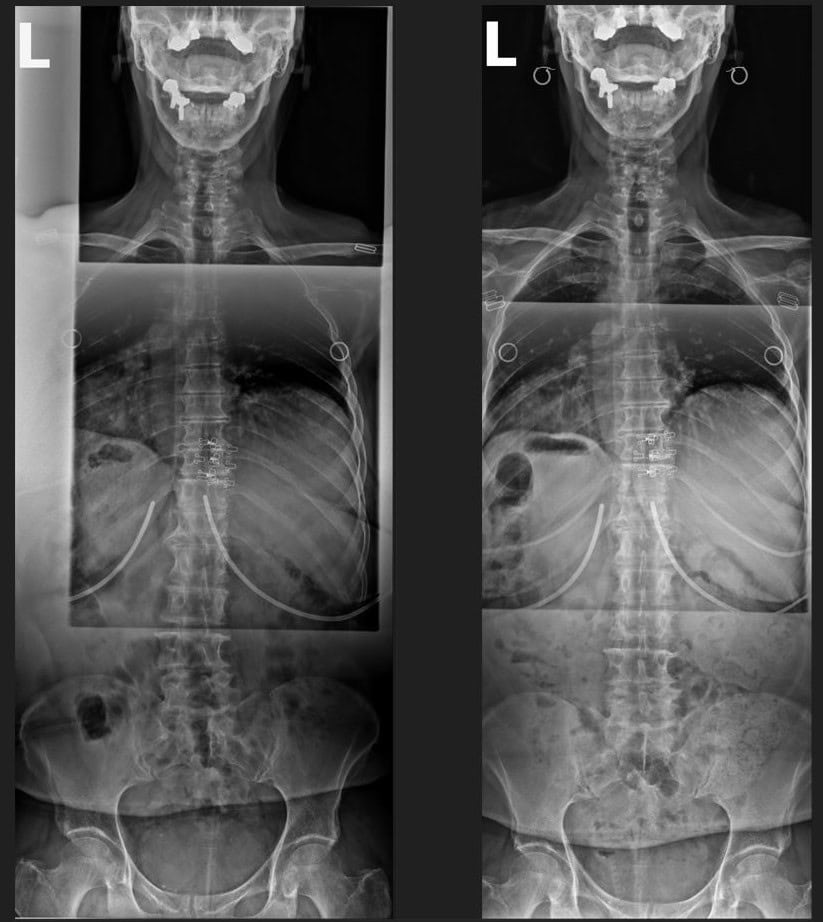

Pre & Post Scan